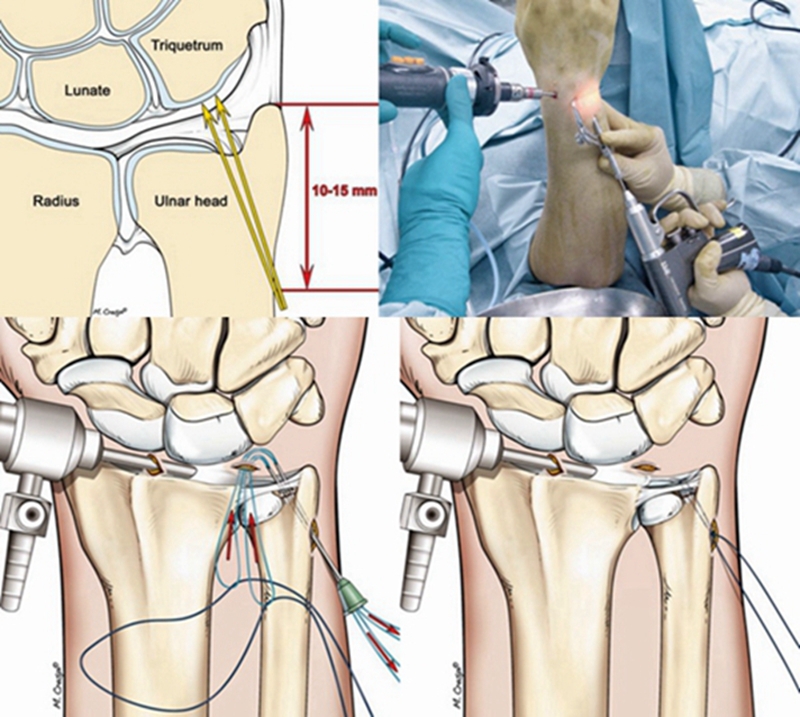

2.手术治疗

TFCCⅠ型损伤首选制动、理疗、口服非甾体抗炎镇痛药及关节腔激素注射等保守治疗,保守治疗超过3个月后无效行手术治疗。

ⅠA及ⅠD型损伤多采用清理、修整术;

ⅠC型若为孤立性撕裂,可单纯清创治疗,若为完全性撕裂,需手术切开修复;

ⅠB型损伤手术治疗多采用缝合修复术。

TFCCⅡ型损伤,对症状持续存在,经保守治疗无效者可行腕关节镜手术。

ⅡA、ⅡB、Ⅱc型损伤:腕关节镜下清创术及软骨成形术;若合并尺骨撞击或尺骨正变异者,行关节镜下清创术结合尺骨头部分磨除术(Wafer术)。